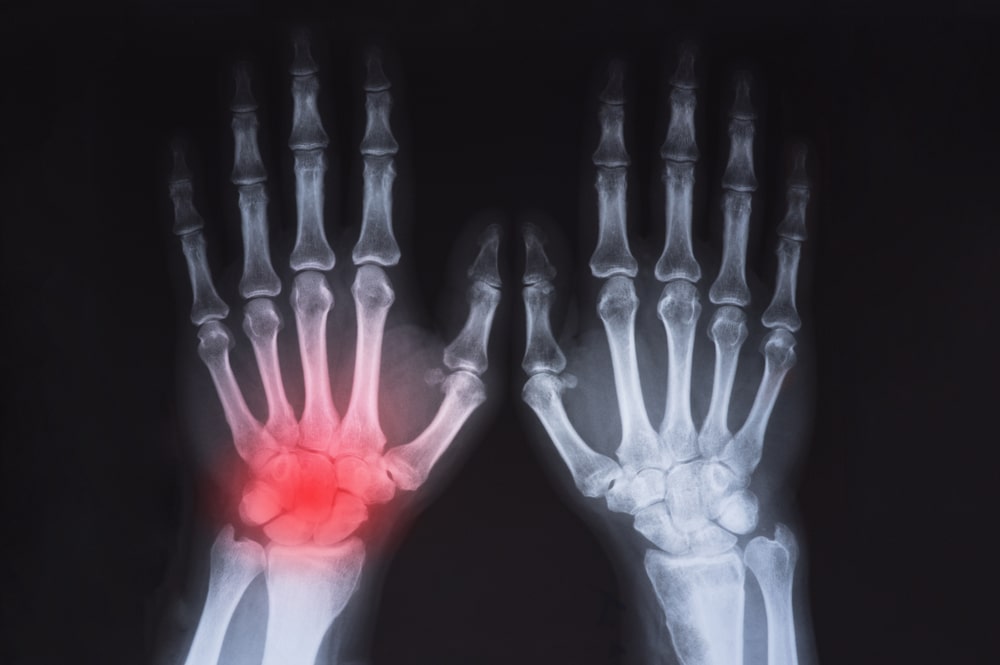

Fractures of the Hand and Wrist

Carpal fractures